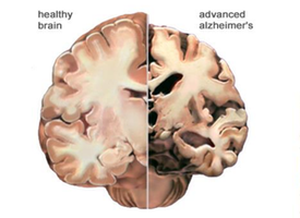

Predicting conversion to Alzheimer's Disease in individuals with Mild Cognitive Impairment

Machine Learning. Random Forests.